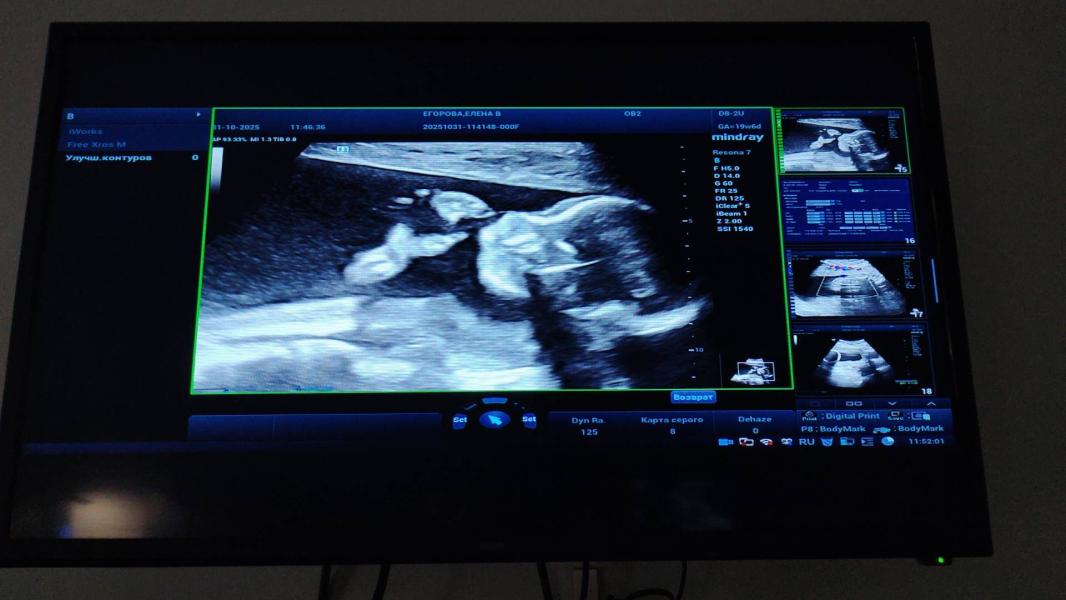

Потому-что то угроза с начала ,то сейчас низкая плацента не поднялась еще ..и что б не было отслойки надо беречь себя и пузожителя

Поэтому пол нам неважен 🙏❤️❤️🔥